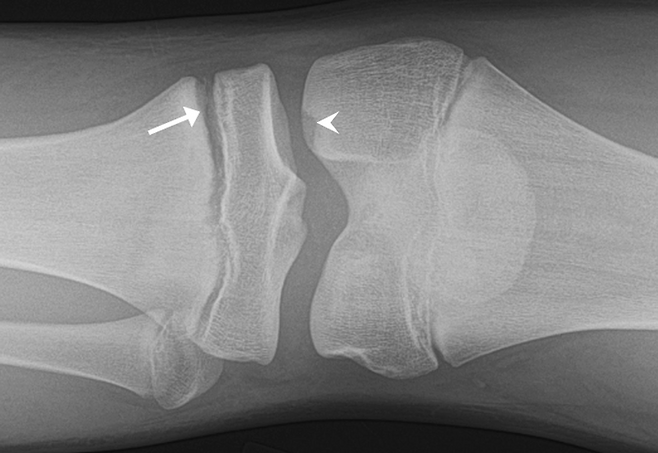

성장판이 닫히기 직전에는 몇 가지 뚜렷한 신호가 보인다. 먼저, 3개월 단위 키 성장 속도가 1cm 미만으로 떨어진다면 이미 성장판 활동이 둔화된 것으로 볼 수 있다. 또 사춘기 초기에 여아는 가슴 발달, 남아는 음성 변화와 체모 증가가 일어나면서 성장 속도가 잠시 급등하지만, 이 시기가 지나면 곧 성장판이 닫히는 단계로 접어든다. 이때 부모가 “이제 클 때가 왔구나”라며 방심하면 이미 막바지일 수 있다. 병원에서는 손목 X-ray 촬영으로 뼈 나이(bone age)를 측정해 성장판이 얼마나 남았는지 확인할 수 있다.